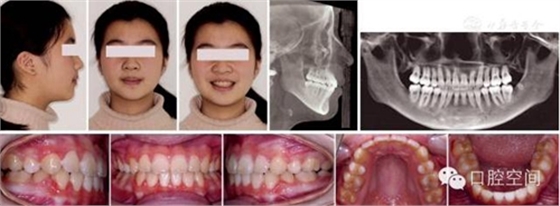

女性,11歲,表現(xiàn)為骨型Ⅱ類錯(cuò)頜畸形,高角,下頜后縮,上下牙弓前突。X線片顯示正處于生長(zhǎng)發(fā)育高峰期。治療前面頜像及X線片見圖2。通過拔除4個(gè)第一前磨牙,應(yīng)用標(biāo)準(zhǔn)方絲弓定向力技術(shù)矯治,并在上頜第一磨牙近中植入種植體。初始弓絲上頜為0.017×0.022英寸不銹鋼方絲(1英寸=2.54 cm),下頜為0.018×0.025英寸不銹鋼方絲,佩戴高位J鉤牽引頭帽12小時(shí)/天,先牽引尖牙往遠(yuǎn)中,再換用0.020×0.028英寸和0.019×0.025英寸不銹鋼方絲分別彎制關(guān)閉曲內(nèi)收上下切牙關(guān)閉間隙,在內(nèi)收前牙的同時(shí),對(duì)上頜后牙進(jìn)行垂直向的主動(dòng)壓低。間隙關(guān)閉后應(yīng)用10-2支抗預(yù)備系統(tǒng)直立下頜后牙,上頜始終通過高位J鉤牽引頭帽進(jìn)行垂直向控制。最后下頜換用0.0215×0.028英寸全尺寸弓絲穩(wěn)定下牙列,使用Ⅱ類牽引和垂直牽引,對(duì)Ⅱ類關(guān)系進(jìn)行過矯正。治療中面頜像見圖3。通過25個(gè)月的矯治,拆除矯治器,制作佩戴保持器。治療后FMA減少了1°,F(xiàn)MIA和Z角均接近正常值(表3),下頜骨垂直向生長(zhǎng)明顯,治療后面型明顯改善,咬合關(guān)系良好。治療后面頜像及X線片見圖4,治療前后頭影測(cè)量對(duì)比圖見圖5。

圖2典型病例治療前面像及X線片